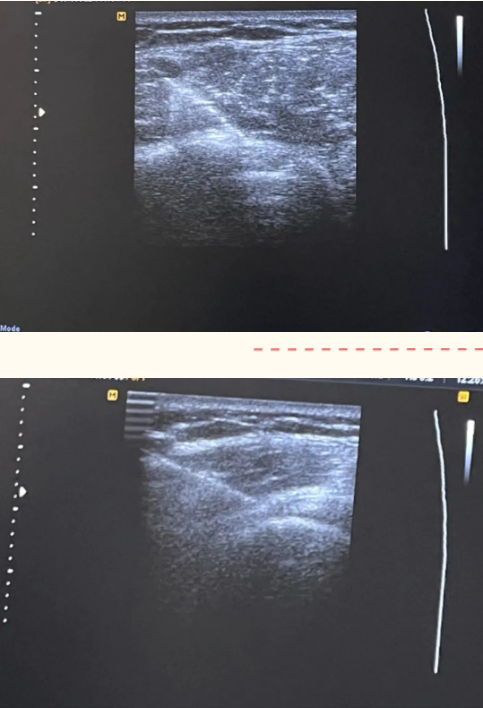

疼痛科负责人崔家平带领团队,采用可视化技术在肌骨超声的引导下将消炎镇痛液注入肱二头肌长头肌腱、肩胛下肌肌腱、岗上肌肌腱、肩峰下滑囊、喙突下滑囊等病变组织周围。通过一次肌骨超声引导的注射治疗,患者肩部疼痛明显减轻、术后即刻肩关节功能得到明显改善。

术中精准定位情况